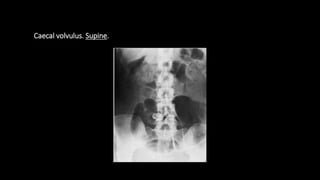

 Caecal volvulus

Caecal volvulus. Supine.

 Caecal volvulus •Associated with degree of malrotation • Accounts for less than 2% of adult intestinal obstruction • Age -30-60 years Diagnosis • Pole of the caecum and the appendix lie in LUQ(50%) • Caecum twists in axial plane and lies in the RLQ(50%) • One or two haustral markings can usually be identified • Seen as large gas filled or fluid filled viscus • Identification of adjacent gas filled appendix confirms the diagnosis • Left half of colon is usually collapsed

• 55.